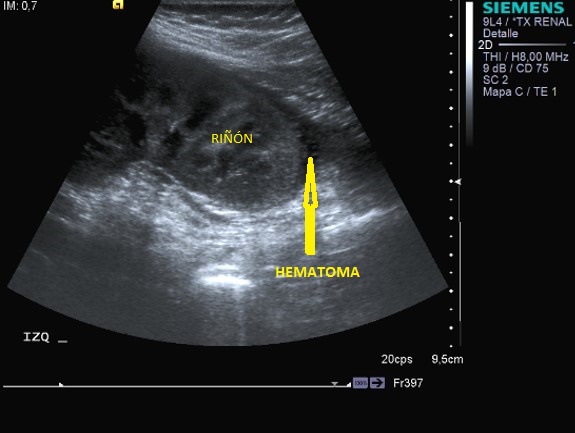

Traumatismos Renales:

Los hematomas renales Pueden ser hipoecogénicos o hiperecogéncios y homogéneos.

Los hematomas subcasulares son colecciones perirrenales que aplanan el contorno renal adyacente.

Hematoma perirrenal